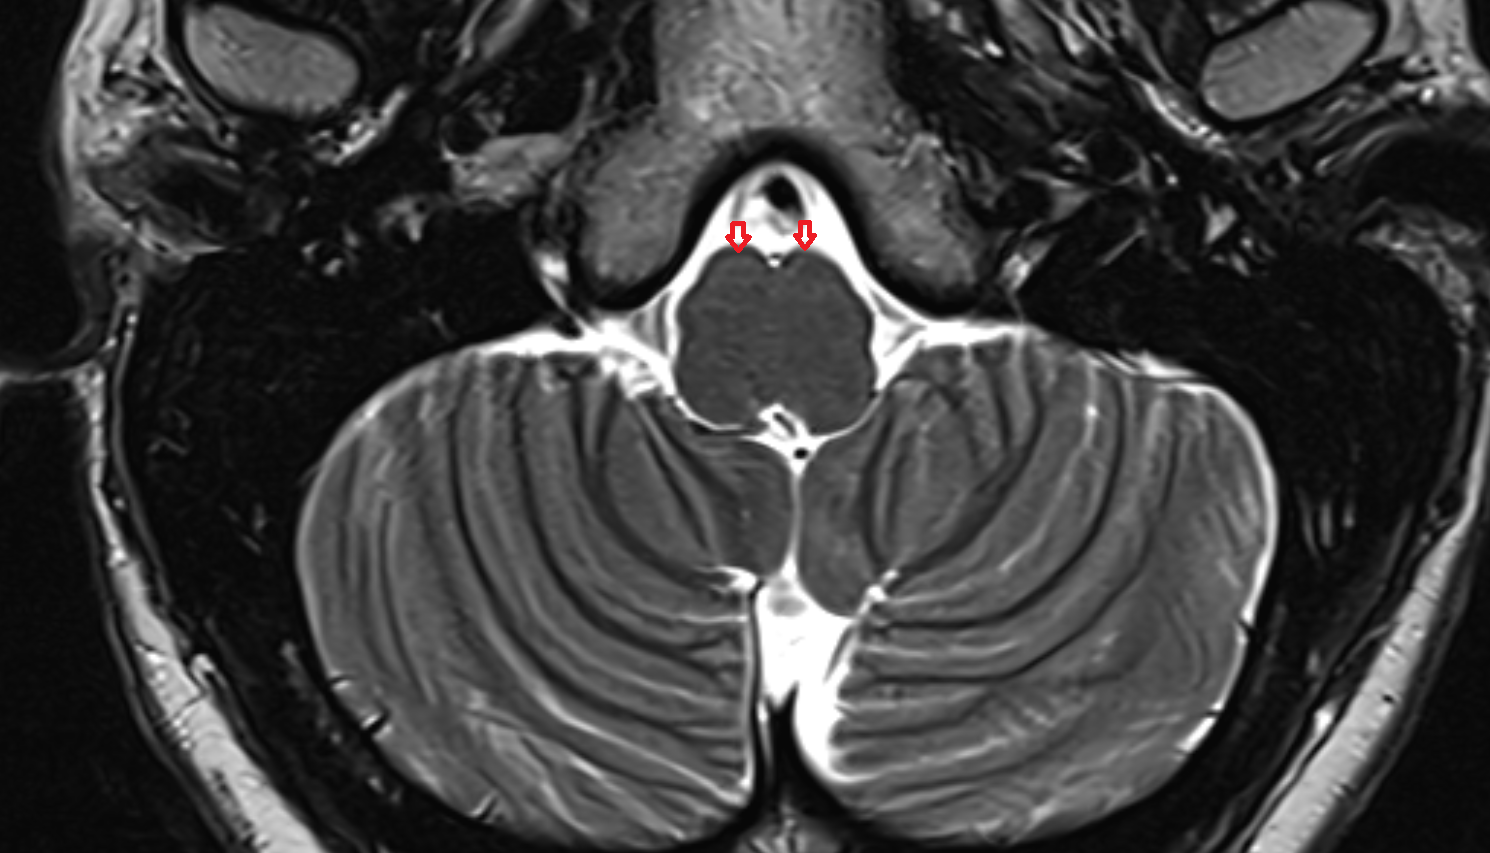

- Median aperture of fourth ventricle (foramen of Magendie)